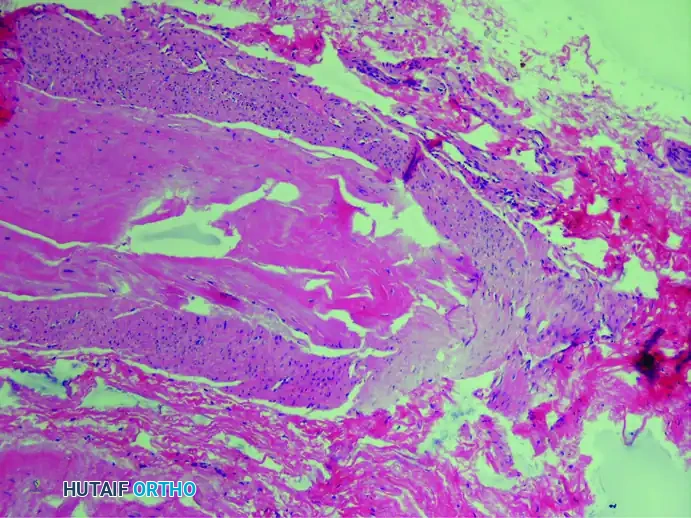

3. Axonal Demyelinization and Degeneration

Secondary to the chronic compression and ischemia, there is profound demyelinization and degeneration of the nerve fibers. Histological stains specific for nerve tissue reveal a significant decrease in the total number of viable axis cylinders.

(Bielschowsky stain showing missing axons and severe degenerative changes)